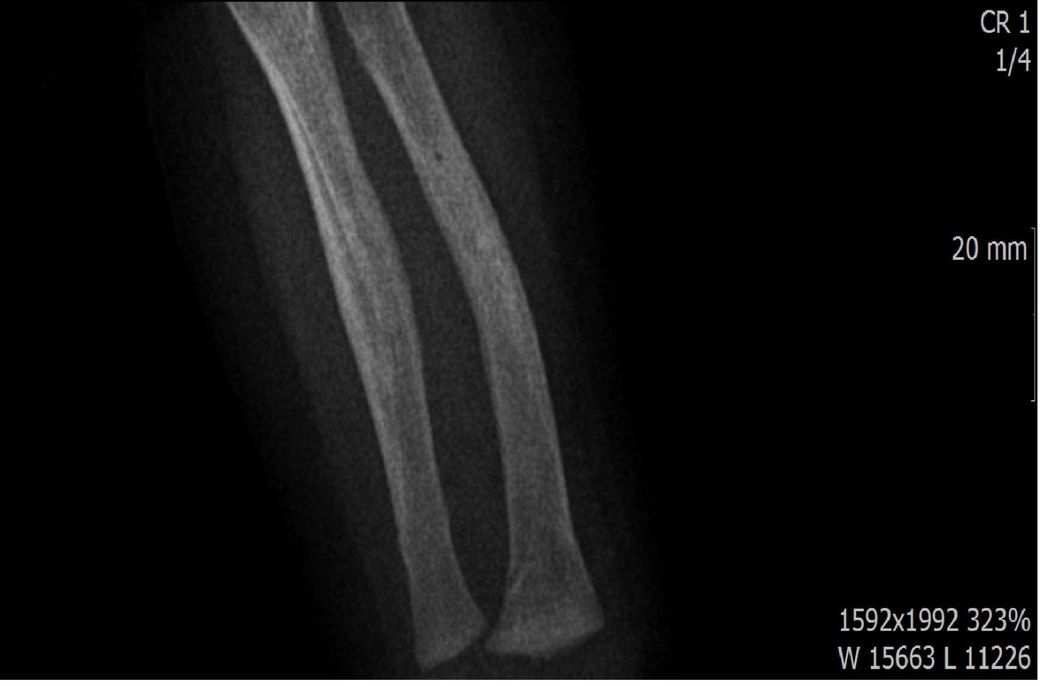

다름이 아니라, 첨부드린 엑스레이(X-ray) 사진처럼 골절 사실을 알게 되고 골절 발생 시점 대략적으로나마 추정시기를 파악하려고 문의 드리게 되었습니다

1) 3월 30일 촬영한 X-ray만으로 정확한 골절 시기를 100% 특정하는 데에는 한계가 있다는 점 충분히 인지하고 있기에 촬영날짜 기준으로 대략적으로 어느정도 시점에서 발생되었을 것으로 추측(ex 당일, 7~10일전, 7~14일 전, 10일 ~ 20일전, 14일 ~ 30일전 등등등)되는지 이해하고 싶습니다.

• 4번 째 사진

하지만, 아예 불가능한건 아니고 골절선이 얼마나 뚜렷하냐, 골막 반응이 보이느냐, 연골성 가골 형성이 있느냐 등으로 골절 시기를 추정해볼 수 있습니다.

골절선이 뚜렷하면 0~1주, 골막 반응이 시작되면 1~2주, 연골성 가골이 형성되기 시작하면 2~3주, 가골이 명확해지면 3~6주 정도로 추정할 수 있습니다.

골절선이 흐려졌고 가골이 형성되기 시작하는 2~3주경이 아닌가 의심이 되지만 제가 골절을 주로 보는 정형외과 전문의가 아니라서 정확도가 떨어집니다.

짐작하기에 아기가 골절이 있었는데 언제 생겼는지를 모르시는 상황으로 보입니다. 그런데, 이정도 골절이면 아기가 팔을 못썻을태고 붓기가 심했을텐데 골절 시기가 파악이 안되시는걸까요?